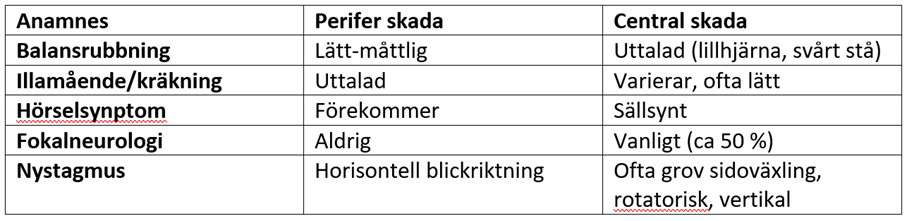

Vilka skillnader kan vi i regel se mellan perifer yrsel och central yrsel?

- Ofta akut insjuknande med huvudvärk och neurologiska bortfall

- Nystagmus

- Är ofta vertikal

- Riktningsväxlande

- Grova fasen mot skadesidan

- Ej uttröttbar och dämpas inte av blickfixation

Vad beskrivs?

Central yrsel